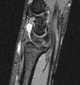

Intra-articular ganglion